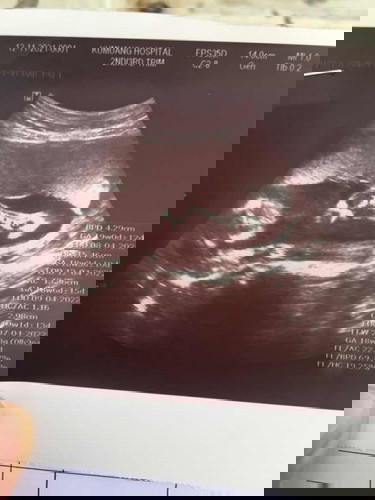

เด็กน้อย22W ไปซาวด์มายกขาไม่ให้เห็นเลย ญหรือช นะ🥰